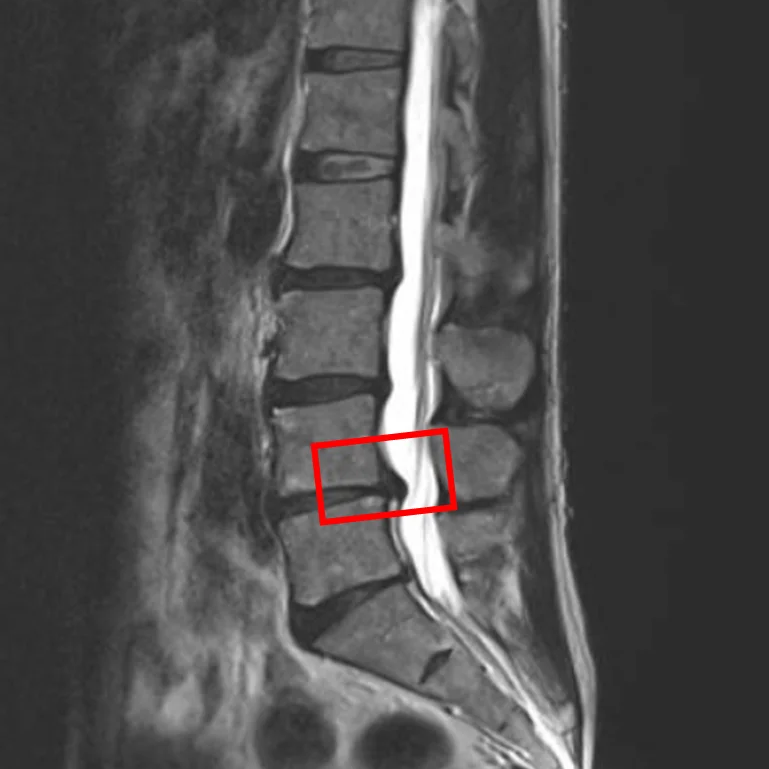

По данным МРТ и результатам осмотра пациента выявлена межпозвоночная грыжа диска L4/L5, дегенерация межпозвоночных дисков L2/L3, L3/L4 и L5/S1.